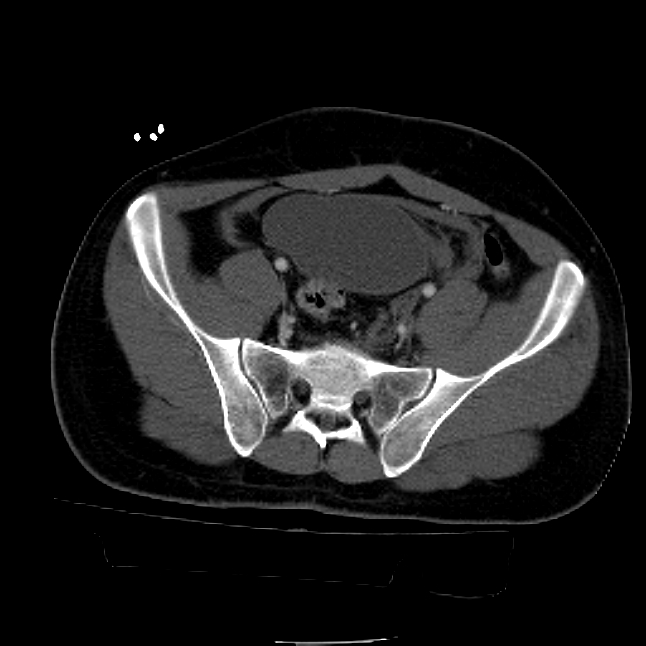

25 yo brittle diabetic, became hypoglycemic and passed out on his motorcycle. Sustained bilateral lateral Hoffa fractures with associated LCL injury on the right and right distal radius fracture. I have questions regarding his pelvic ring/acetabular fracture on the left. Appears to be a very low posterior column fracture with associated posterior wall, marginal impaction. Superior and inferior rami fractures as well on the left giving him a floating segment of inf ramus/ischium/posterior column, but no detectable posterior ring injury. Should the posterior column/posterior wall fracture be addressed surgically because of the marginal impaction? Or is this fracture low enough to be treated non-operatively? I appreciate the input.

It's an interesting case. The plain films show the impaction, but most of the joint looks pretty good. The CT cuts look awful, though.

The impaction is so big I don't think I would ignore it. It IS down low, but it takes up almost the whole southern hemisphere of his joint.